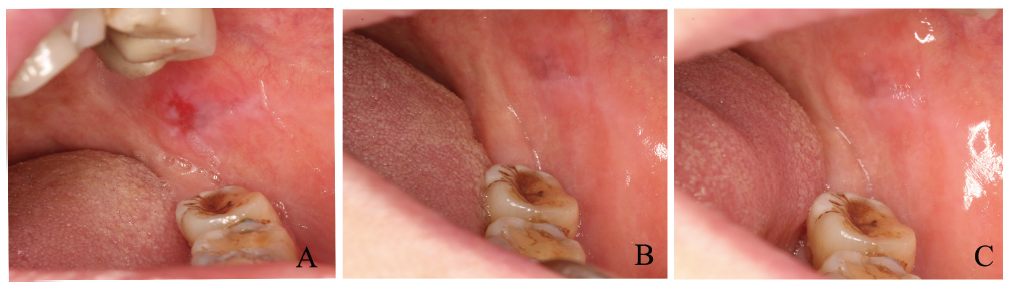

四、试验组患者典型案例治疗效果展示

试验组1例患者治疗前后的对比见图1

图1 试验组1例患者治疗前后对比

A:治疗前;B:治疗2周后;C:治疗4周后